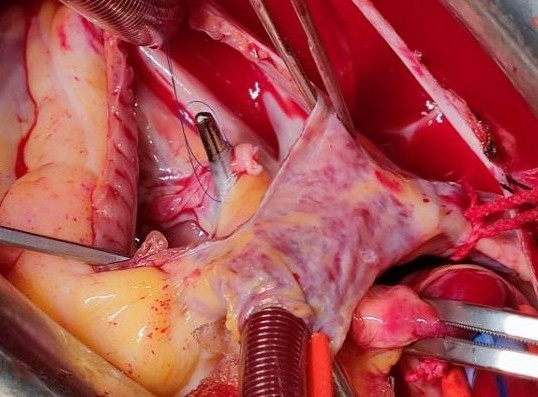

1 资料与方法患者女性,19岁,因“突发胸痛14 h”入院。患者14 h前无明显诱因出现胸骨后疼痛,呈紧缩感,伴有胸闷、呼吸困难,间断咳嗽。近期有听力下降、腹泻病史。8 h前就诊于外院时查体:体温测不出,Bp 53/36 mmHg(1 mmHg=0.133 kPa),呼吸40次/min, 脉搏137次/min,SPO2 93%,神志淡漠,全身皮肤湿冷,黏膜无黄染及出血点,颈静脉无怒张。听诊双肺呼吸音粗,可闻及满肺湿啰音,心音不清,腹部查体无异常,双下肢足背动脉搏动对称。化验结果提示WBC 29.3×109/L,NE 85.4%,TnT 93 ng/L,pro-BNP 2 047 pg/mL,PCT 0.11 ng/mL, 血气分析:pH 7.349,PCO2 31.2mmHg,PO2 67.2 mmHg,HCO3- 17.2 mmol/L,Lac 5.7 mmol/L。心电图提示:窦性心动过速、AVR导联ST段抬高,余导联ST段压低;床旁心脏超声提示EF 52%,二尖瓣中度返流、三尖瓣中重度返流,未见室壁节段性运动性异常。考虑心源性休克,原因尚不明确,给予机械通气、血管活性药物、补液等抗休克治疗,同时联系本院急诊ECMO团队,本院急诊ECMO团队到达现场后,患者突然出现室颤,给予胸外按压及电除颤后逐渐恢复窦律,立即进行V-A ECMO上机指征及预后评分SAVE评分评估,符合V-A ECMO上机适应证,约30 min成功上机运转,流量3.5 L/min,复查外周动脉血气分析: pH 7.305,PCO2 21 mmHg,PO2 73.4 mmHg,HCO3- 10.5 mmol/L,Lac 8.4 mmol/L。后转运至本院急诊病房,转运途中行生命体征、血气分析、ACT等常规监测,至病房后患者ECMO支持下血压仍需大剂量血管活性药物维持且脉压差较小,观察ECMO动静脉管路颜色极为接近,床旁经胸心脏超声提示主动脉瓣重度返流,为明确原因立即行急诊CT检查及床旁经食道超声心动图检查。本院肺CT(图 1)提示肺水肿,床旁经胸心脏超声提示主动脉瓣大量返流但心室收缩可,请超声影像科进一步行床旁经食道超声检查提示无冠窦呈瘤样凸向右房侧,瘤壁上可见宽约0.6 cm破口;主动脉瓣舒张期无冠瓣脱向左室流出道侧(图 2、图 3)。立即请心血管外科会诊,急诊行主动脉瓣机械瓣膜置换术+主动脉窦修补术+房间隔造口术+主动脉球囊反搏置入术+心脏起搏器置入术,术中探查与经食道超声所见相符(图 4、图 5),考虑左心功能差,左心压力较高,行房间隔造口术。术后复查胸片肺水肿基本消失(图 6),继续呼吸机与ECMO支持,因患者肺功能良好,自主呼吸良好,为减少呼吸机相关肺损伤、呼吸机相关肺炎等发生,术后第4天神志清醒后拔除气管插管,机械通气减轻左心前后负荷的作用去除后,继续ECMO与IABP支持,ECMO增加左心后负荷时IABP可降低左室后负荷,达到左心减压的目的,术后第10天心功能恢复,下调ECMO流量后循环可维持,予以撤离ECMO,术后第12天撤离IABP,后停用肝素持续泵入抗凝,达肝素皮下注射联用华法林口服抗凝3 d后,单用华法林口服抗凝,维持INR达标,在康复期间患者活动时左下肢疼痛,左侧足背动脉搏动减弱,下肢动静脉超声提示左侧股浅动脉血栓形成,期间增加华法林剂量后血栓未见明显变化,后行下肢股浅动脉切开取栓术,术后33 d患者完全康复顺利出院。

| 图 5 术中修补破口 |

因患者生命体征难以维持并出现室颤,经初始评估符合V-A ECMO上机适应证,预后评分生存率较高,遂紧急行V-A ECMO,上机初期动静脉导管内颜色差别较明显,很快两导管内颜色难以区分,考虑原因为充分氧合的左心血通过破口直接进入右心房被引出,自身形成“再循环”使得动静脉导管颜色相近。根据2021年ELSO成人心脏病患者V-A ECMO指南,对ECMO功能有影响的病因如主动脉瓣关闭不全为V-A ECMO潜在禁忌证[9],理论上患者行V-A ECMO后主动脉与右心之间的压力差会进一步增大,左向右分流增加,心源性休克进行性加重且随时可能出现心脏停搏,但患者已出现室颤,病因未明确情况下经目前治疗仍随时会出现呼吸心搏骤停,且通过精确的ECMO流量滴定可减少右心容量负荷,同时相对减小主动脉与右心之间的压力差,为后续寻找病因及治疗争取时间。V-A ECMO也同样适用于心脏术后心功能尚未恢复的患者,本例患者因术后心功能较差未能立即撤机,继续V-A ECMO支持治疗,待心功能恢复后才撤机。V-A ECMO的适应证在临床上不断被拓宽,其精准使用可以为存在相对禁忌证的患者的后续诊治争取时间。但本例患者治疗期间也出现了V-A ECMO的常见并发症:左心压力增加及下肢动脉缺血。V-A ECMO辅助下因左心室后负荷增加引起左室扩张,易出现左房增大、肺水肿、血流瘀滞形成血栓等,不利于心肌的恢复,术中行房间隔造口术减轻左心压力;术后出现下肢动脉缺血,股浅动脉内出现血栓经抗凝治疗无效后行下肢动脉切开取栓术。